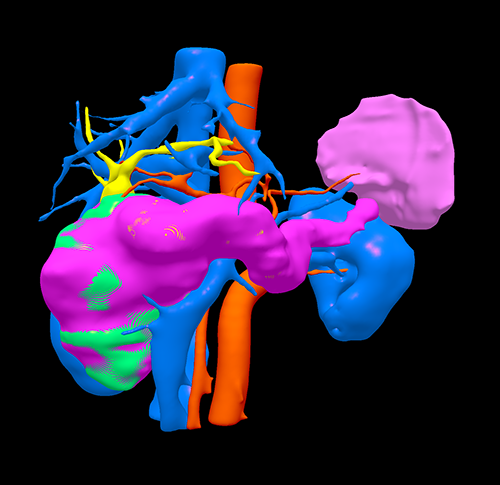

三维重建

胰头囊腺瘤---胰十二指肠切除